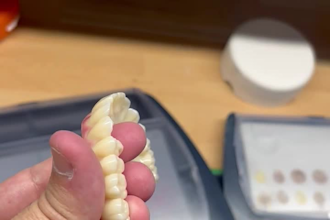

I will do dental prosthesis crown design using exocad, 3shape, inlab and cerec

From $20